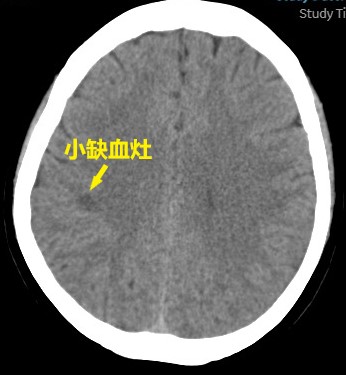

患者头颅CT提示基底节和反射冠多发小斑片缺血灶,双侧基底节钙化灶,排除脑桥小脑角处占位性疾病,骨窗排除中耳炎等疾病。电测听提示双耳听力在20-30分贝之间。